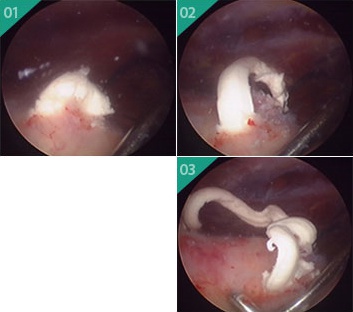

가장 확실한 치료는 관절경을 통한 수술적인 치료 입니다. 일상생활에 영향을 받을 정도로 통증이 심한 경우는 수술적 치료를 반드시 고려해보아야합니다. 이러한 수술의 핵심 개념은 '감압' 에 있습니다. 칼슘으로 압력이 올라간 관절의 압력을 낮춰줄 수 있습니다.